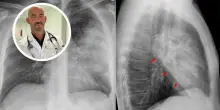

Botulino, Bassetti su medici indagati: "Come si fa a non riconoscere sintomi?"

(Adnkronos) - "Serve sensibilizzare gli operatori a fare prevenzione" dice all'Adnkronos Salute il direttore Malattie infettive dell'ospedale policlinico San Martino di Genova